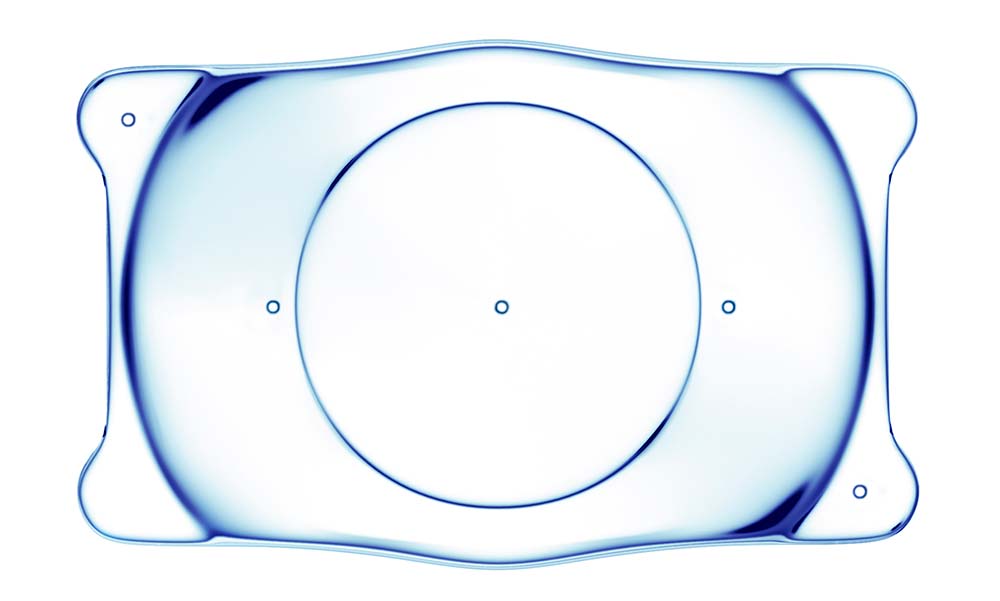

Implantable Collamer Lens surgery (ICL), as the name itself suggests, is a procedure, wherein a pair of lens is implanted into the eyes which do not require to be removed like normal contact lenses. These lenses are similar to contact lenses but are inserted within the eyes for long-term vision correction. These lenses, therefore, work with the natural lens of your eyes to improve your vision. During the procedure, the lens is inserted between your iris and your natural lens thru a tiny incision near the cornea.

- Through the incisions, he injects the lens into the eye. The lens is positioned behind the iris and in front of the natural lens.